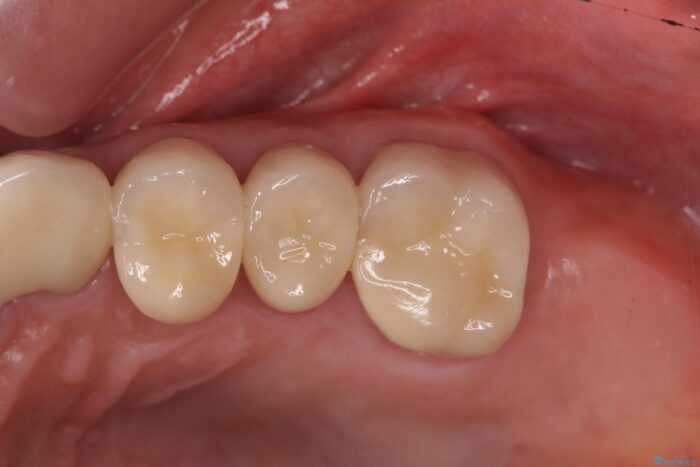

清掃しやすいクラウンへ

クラウンが装着されておらず、つぎはぎだらけの処置歯を、精度の高いセラミッククラウンを用いて歯ブラシのしやすい環境整備を行っていきます。

セラミッククラウンの治療は、天然の歯のような審美性を回復できることも大切ですが、精度が高くきっちりと歯ブラシを行いやすい状態を整えることで虫歯や歯周病の再発リスクを下げることも非常に大切です。